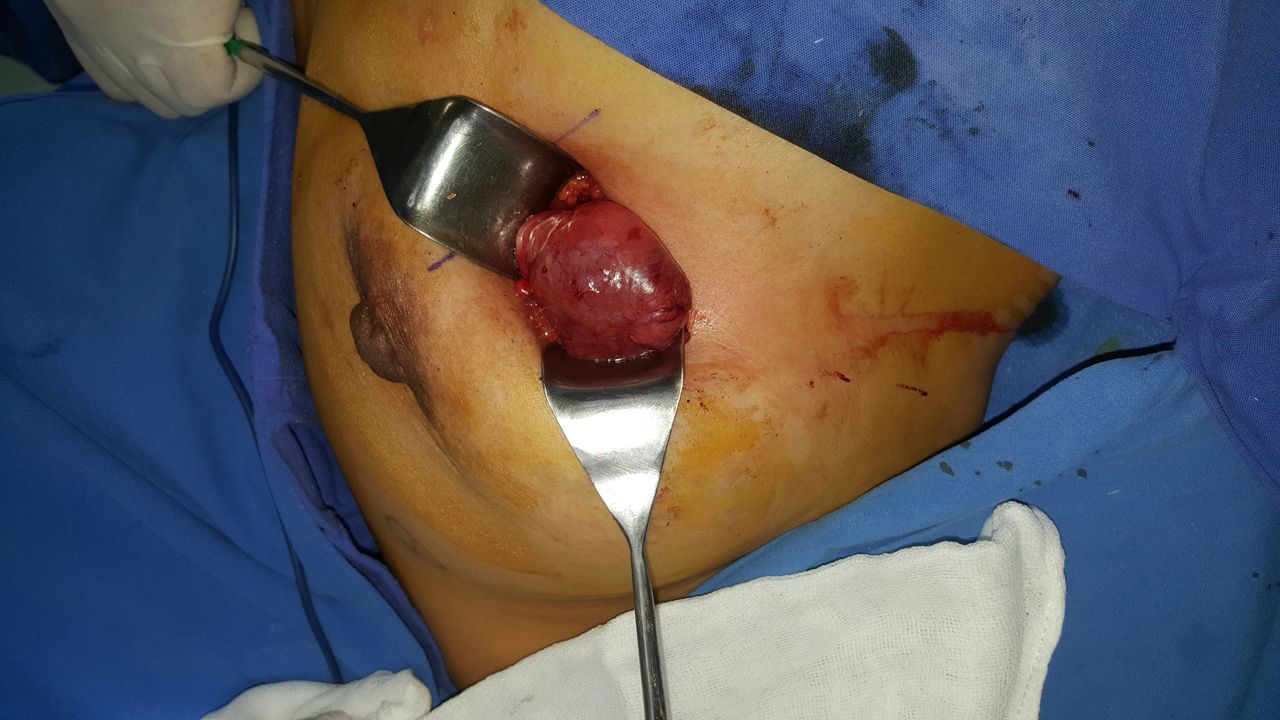

Quiero expresar mi más sincero agradecimiento al Dr. Millán. Me realizó la cirugía para retirar un fibroadenoma de aproximadamente 4 cm en mi mama izquierda y desde el primer momento me sentí en excelentes manos.

Siempre fue sumamente empático, amable y profesional, explicándome todo con calma y brindándome mucha tranquilidad durante todo el proceso. La cirugía fue impecable y cuidó muchísimo cada detalle para que la herida quedara no solo funcional, sino también estética, algo que valoro profundamente.